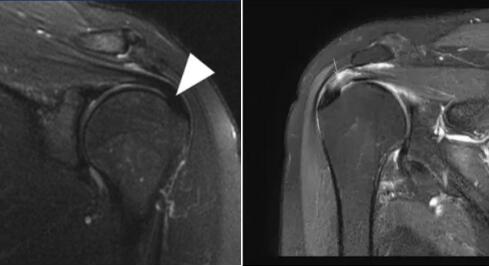

正常肩袖核磁共振图像 肩峰撞击后导致肩袖上表面撕裂